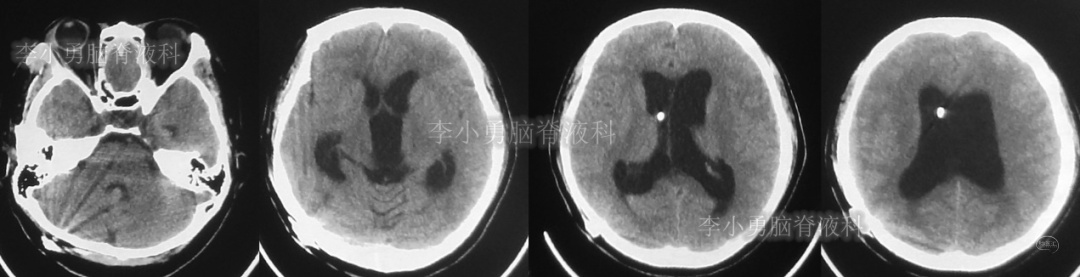

患者于2018年1月29日,突发头痛、头晕、恶心、呕吐,并高热40度。在当地医院门诊输入4天抗生素后发热缓解,但出现了双眼不能上视(眼球不能向上看)。5天后即2018年2月3日,在当地的第1家医院:浙江省海宁市某医院行头颅CT(图-1)发现脑室扩张,当地医院诊断为“梗阻性脑积水”。

图-1:2018年2月3日头颅CT